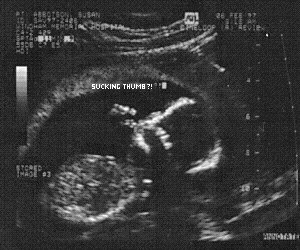

And take a peek at our newest member. A Humu in vitro! #1#2#3#4

As of July 17th, she's a Humu ex-vitro.